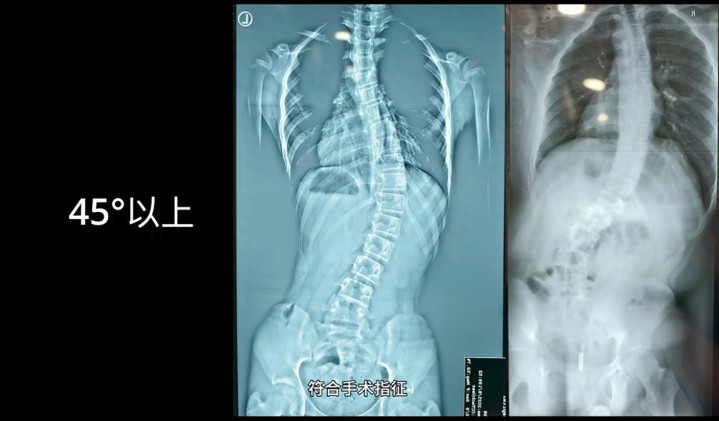

据中国后生报报说念,脊柱侧弯已成为继近视和臃肿后第三大青少年健康威迫,我国中小学生发生脊柱侧弯的东说念主数仍是超越了500万,况兼在以每年30万足下的速率递加。

康复支具在处理脊柱侧弯矫形等医常识题中承担着穷苦变装。不管是骨折还原、关节巩固、脊柱矫形如故怒放挫伤康复,患者通常需要长久指挥定制化的复旧装配。但是,传统康复辅具制作历程却存在明显痛点。